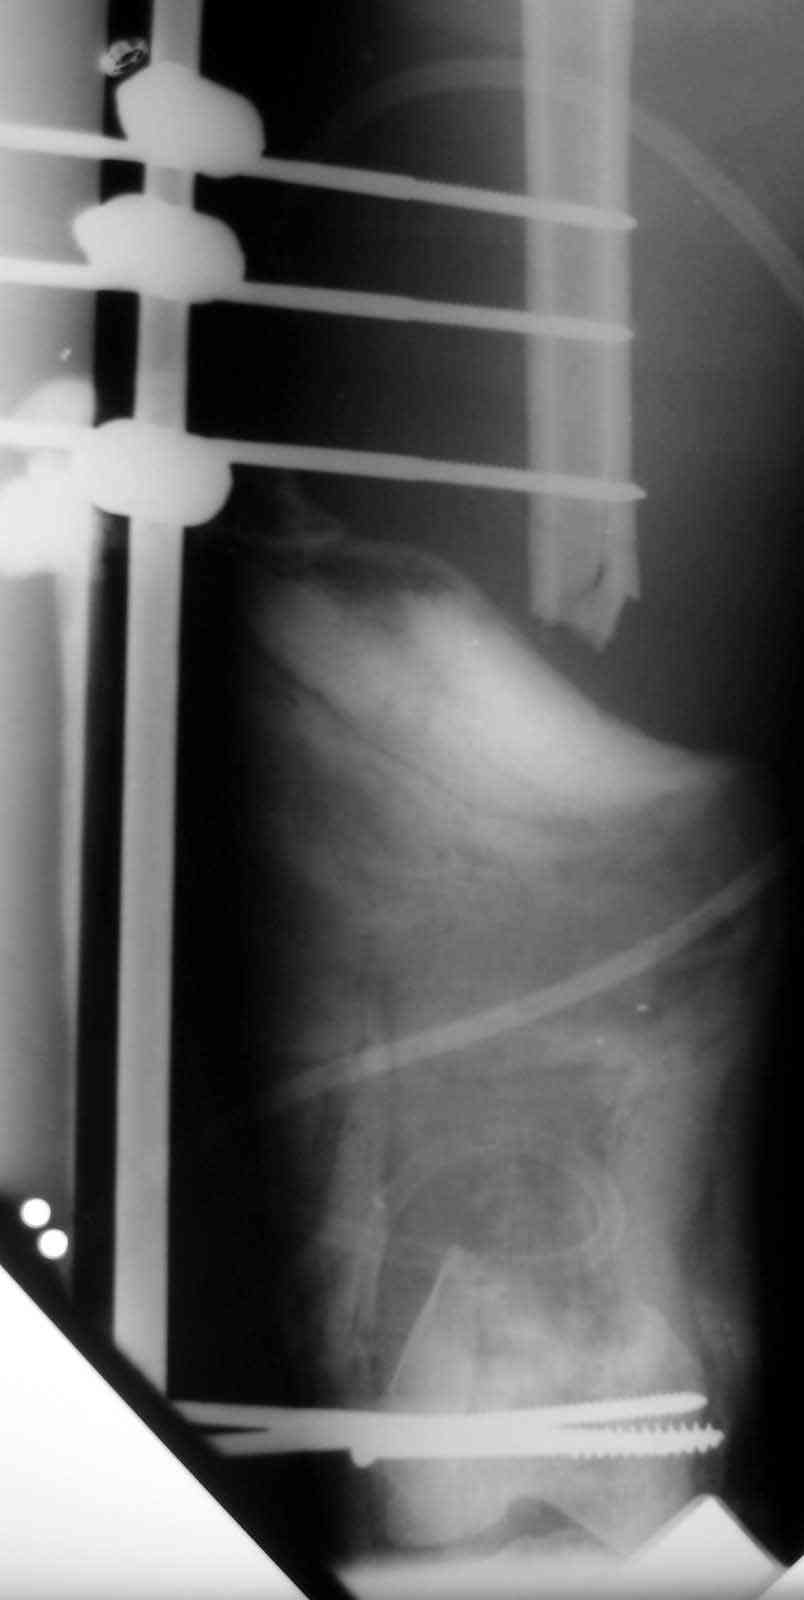

18 ys. old boy with motorcycle accident lost the distal 1/2 of his femur at the scene of the accident.

Debridment and ex. fix done immediately.